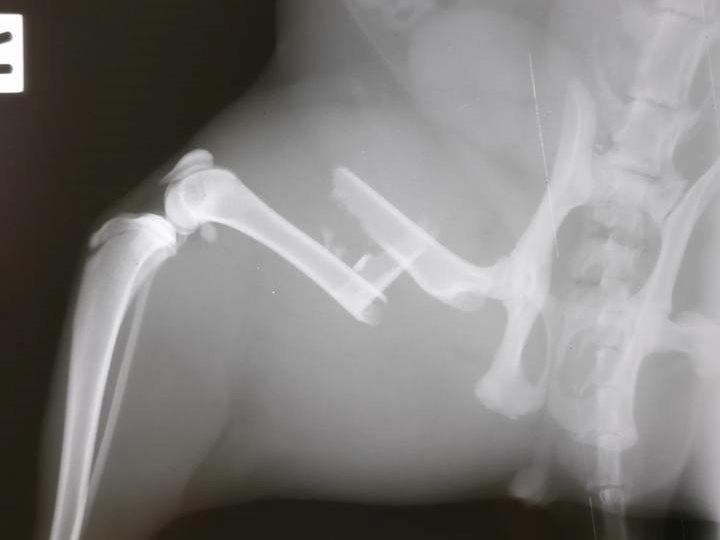

Xrays after the operation  30 August 2017

So here you can see the Rod they inserted into the middle of the bone and attached plates and screws to hold the bone in place.